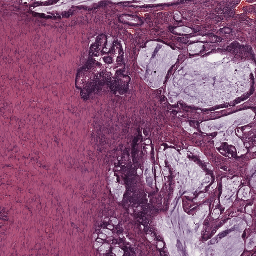

A set of 74 histological slides from 74 patients was prepared from surgically excised rectal carcinomas in patients who had not received neoadjuvant chemotherapy and/or radiotherapy. Slide preparation involved standard fixation of 2m tissue sections and H&E staining. Whole-slide scanning was performed at 200X magnification (pixel resolution = 0.455 m) using a Hamamatsu NanoZoomer 2.0-HT C9600-13 scanner (Herrsching, Germany), which produce 74 gigapixel whole-slide images. Manual annotations of 9 tissue classes were made by an expert using the open source software ASAP555github.com/GeertLitjens/ASAP developed in-house, which included: (i) tumor, (ii) stroma, (iii) necrosis, (iv) muscle, (v) healthy epithelium, (vi) fatty tissue, (vii) lymphocytes, (viii) mucus and (ix) blood cells (see Figure 2). All annotations were successively thoroughly checked by a pathologist and corrections were made when necessary. In the rest of the paper, we refer to this dataset as rectal cancer (RC) data.

2.3 Stain normalization

Stain normalization (SN) involves transforming an image into another image , through the operation , where is a set of parameters extracted from a predefined template image and is the mapping function that matches the visual appearance of a given image to the template image. The parameters are generally defined to capture color information of the main stain components in the image (e.g. H and E). As a result, stain-normalized images will have a distribution of colors that resemble the ones of the template. In Figure 1, images from CRCt and their stain-normalized version based on the WSI template of Figure 2 are depicted.